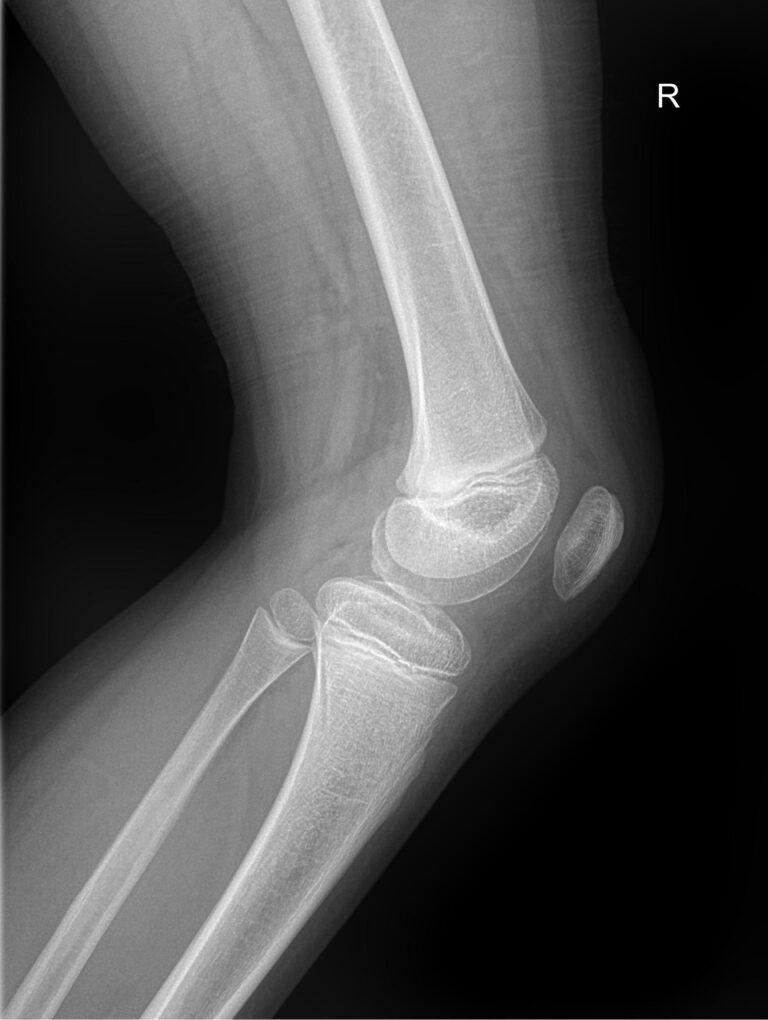

Назад Рентген обоих коленных суставов

Коленные суставы ежедневно выполняют большое количество движений, связанных с ходьбой, бегом, прыжками, приседаниями и подъемом, и выдерживают вес человека, каким бы он ни был. Как и любые другие суставы в теле, они подвержены воспалению и другим патологическим изменениям, а также травмам, инфекциям, новообразованиям и возрастным дегенеративным процессам. Это одни из самых крупных суставов в теле человека.

Первым видом диагностики пациентов с ортопедическими патологиями обычно является рентген. Это простое, быстрое, неинвазивное и безболезненное обследование с высоким уровнем информативности. В большинстве случаев его бывает достаточно для постановки диагноза и выбора тактики лечения. Кроме того, уровень облучения, который получают обследуемые, минимален благодаря современной цифровой аппаратуре.

Что покажет рентген обоих коленных суставов в одной проекции

В протоколе у каждого сустава описывается:

• Состояние мягких тканей;

• Суставная щель ― в норме, расширена, сужена, затемнена, имеет дополнительные включения;

• Состояние суставных  поверхностей и их соответствие друг другу ― несоответствие говорит о вывихе;

• Положение надколенника ― обычное или нет;

• Состояние костной ткани и надкостницы ― могут быть обнаружены участки разрежения, размягчения или других патологических процессов, а также свежие и сросшиеся переломы.